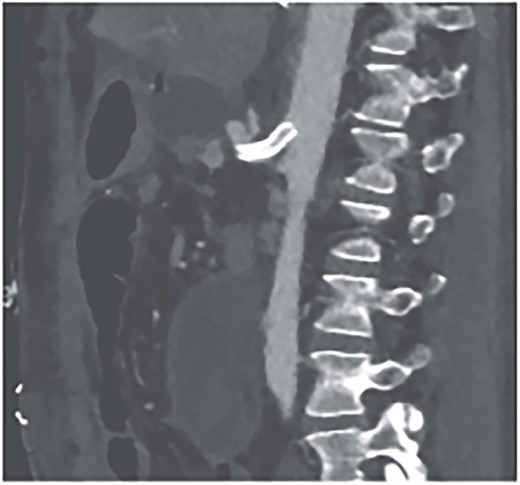

We attributed the recurring aneurysmal bleedings of the pancreaticoduodenal arcade to extensive collateral circulation via the SMA, given an existing stenosis of the celiac trunk, most likely within the framework of a MALS (Fig. 6). To address this cause, a relaparotomy was performed the following day, decompressing the celiac trunk by splitting the median arcuate ligament (Fig. 8). Postoperatively, percutaneous transluminal angioplasty (PTA) with stenting of the celiac trunk was conducted for flow assurance (Fig. 7).

However, on the 16th day following the initial surgery, there was another active bleeding from the pancreaticoduodenal artery, distal to the previously placed coil. This bleeding was also managed interventionally (Figs 4 and 5).

Angiography showing another aneurysm with active bleeding, proximally to the previously coiled site.

Postinterventional angiography, after interventional bleeding control, using coiling.